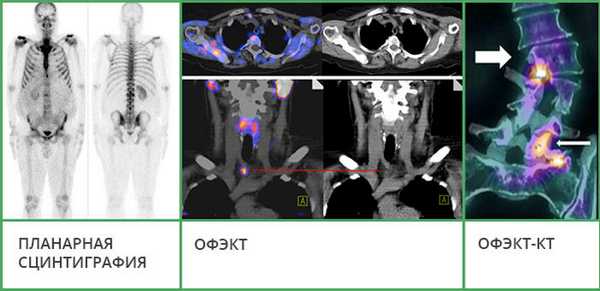

- Планарная сцинтиграфия - наиболее простая методика. Позволяет получать двухмерные снимки, как во время рентгенографии, на которых видно распределение радиофармпрепарата. Этот вид исследования часто используют, чтобы обнаружить в костях первичную злокачественную опухоль или метастазы.

- Однофотонная эмиссионная компьютерная томография (ОФЭКТ) позволяет получить серию смежных двухмерных изображений, на которых также визуализируется распределение радиоактивного индикатора.

- ОФЭКТ-КТ - наиболее информативная методика. Во время исследования данные сцинтиграфии совмещают со снимками, полученными с помощью КТ. Это позволяет получать трехмерные изображения, судить не только о патологических изменениях в костях, но и о точной локализации очагов.